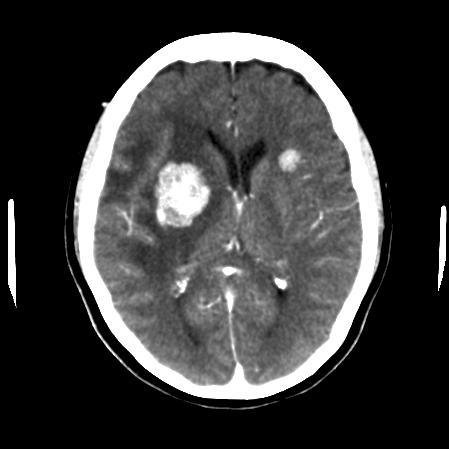

Multiple Brain Mets